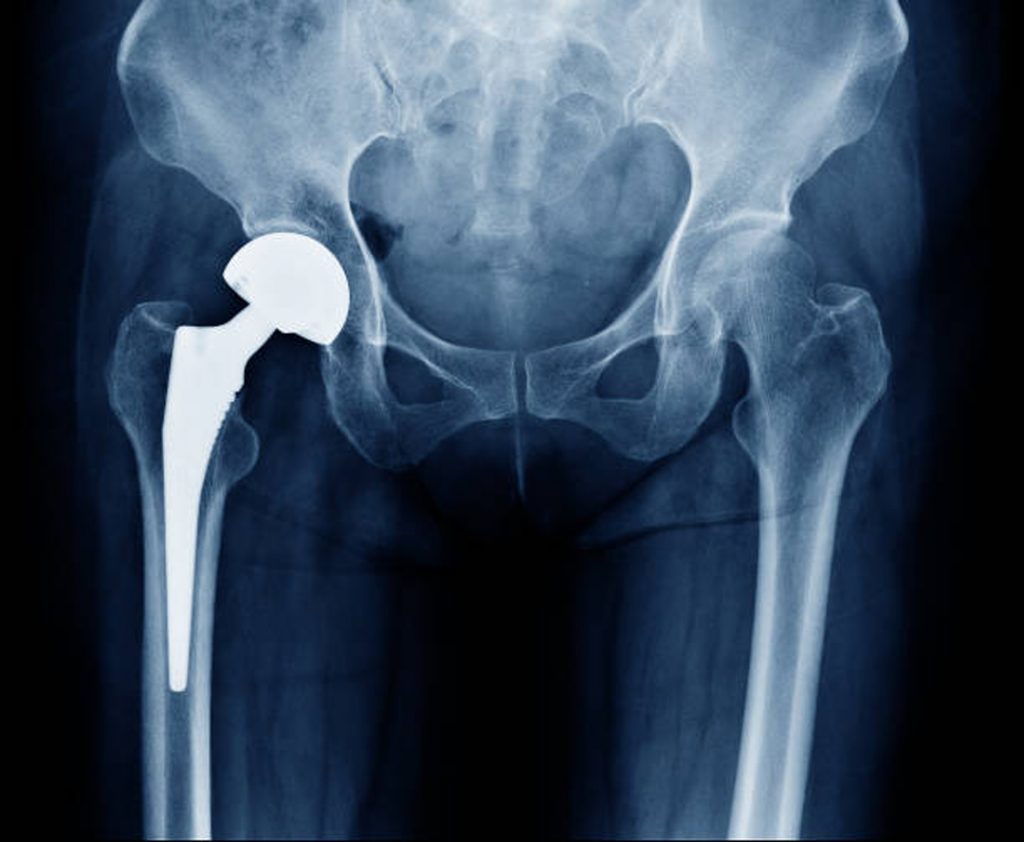

Joint replacement surgery is a surgical procedure that restores mobility and function to a joint that has become damaged or defective. Joint replacement surgery is typically used to replace a joint that is affected by arthritis, injuries, or age.

Joint replacement surgery can provide significant relief from symptoms associated with arthritis, injuries, or age-related damage. In addition, joint replacement surgery can restore mobility and function to a joint that has become damaged or defective. If you find yourself considering joint replacement surgery, be sure to speak with your doctor about your individual situation and ensure that you have all of the information you need to make an informed decision.